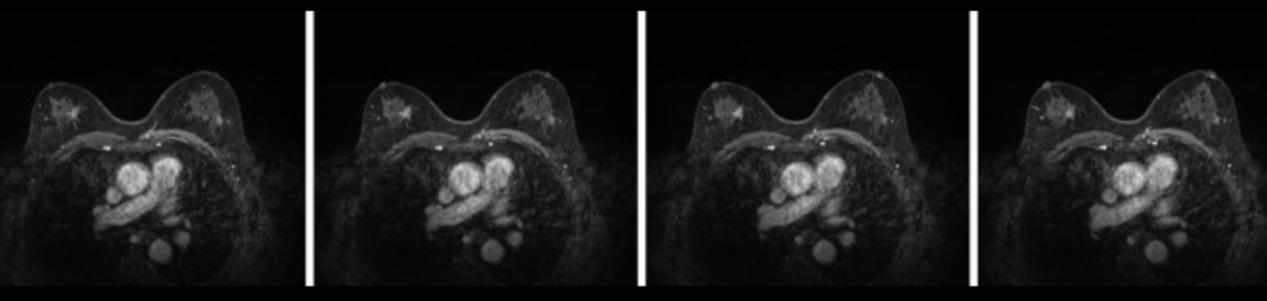

乳腺超声表现为:(1)双侧乳房上外侧象限实性占位(BI-rads4c);(2)左乳12点位置的实性肿块(BI-RADS 4B)。双侧腋下及左锁骨上区淋巴结。右锁骨未见肿大淋巴结(图1)(图2)。乳腺增强磁共振成像(MRI)表现为:右乳上内象限不规则增强(BI-rads4c);左乳上外侧象限斑片状异常信号(BI-rads4b);两个乳房的纤维囊性改变(BI-RADS 2)(图3)。

图3